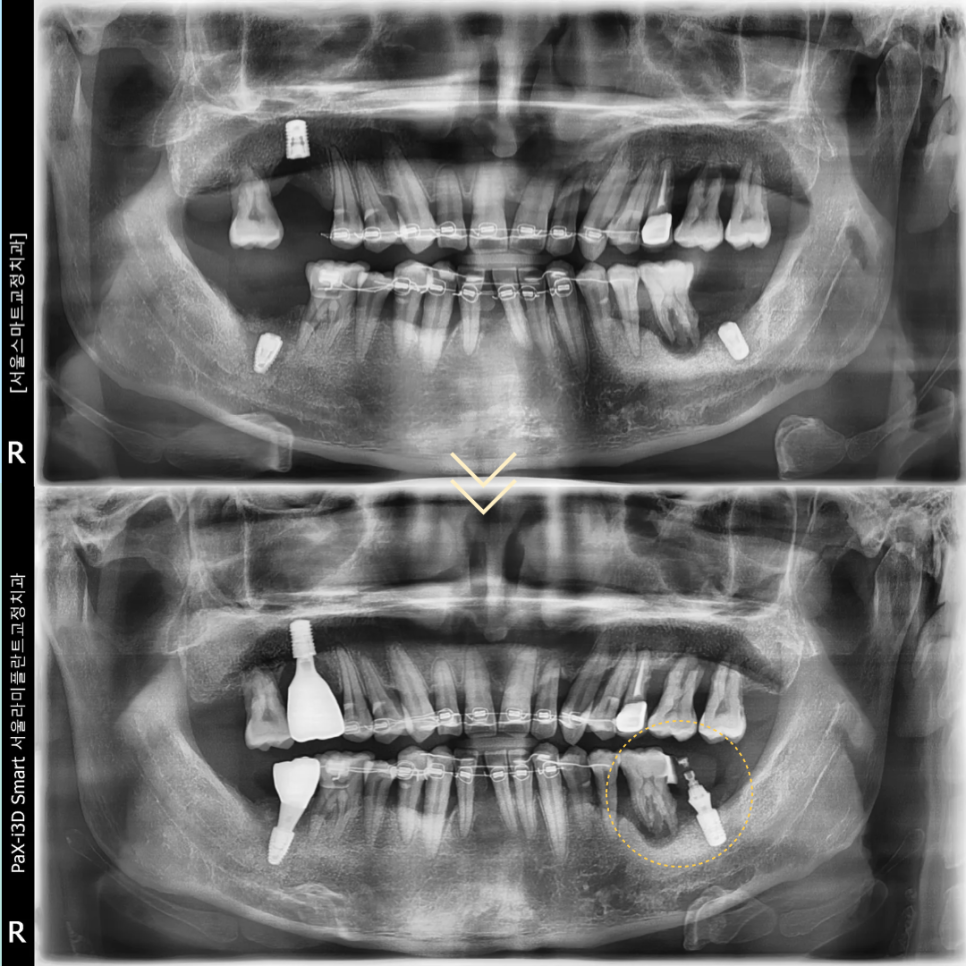

치조골과 임플란트가 골유착되는

치유의 시간을 충분히 기다린 뒤

왼쪽 위 보철도 마무리하였습니다.

마지막으로 왼쪽 아래의 첫 번째 큰어금니도 발치한 뒤

임플란트 식립을 진행하였습니다.

이후 왼쪽 맨 뒤의 임플란트에

장착했던 임시치아는 제거하고

왼쪽의 큰 어금니 부위에 스플린트 브릿지로

최종 보철을 완성하였습니다.

교정과 보철을 동시에 진행함으로써

전체 진행 기간을

불필요하게 늘리지 않으면서도,

임플란트 식립 과정을 효과적으로

연결할 수 있었습니다.

하악 앞니 부위의 경우

식립을 하기에는

남아 있는 치조골의 양이 충분하지 않아

심미적으로 만족스러운 결과를

얻기 어려울 가능성이 높았습니다.

이에 따라 해당 부위는 올세라믹 브릿지로

수복하여 자연스러운 외형과 기능을

동시에 고려한 치료를 진행하였습니다.